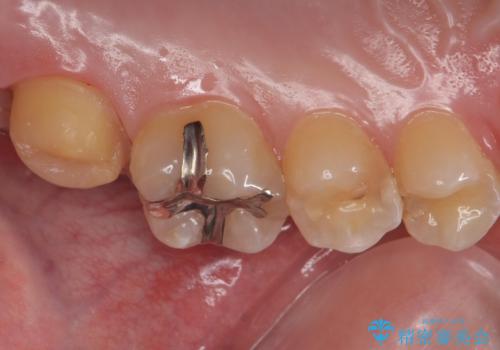

- 奥歯が欠けてしみるとのことで来院された患者様です。

かなり大きな虫歯であることと、清掃不良により歯全体が脱灰していたため、クラウンでの修復処置を行います。

奥に生えている親知らずも清掃不良であったため、今回治療する歯の清掃性を高めるために抜歯を行います。

かなり大きな虫歯でしたが症状も出ず、根管治療もせずに終えることができました。